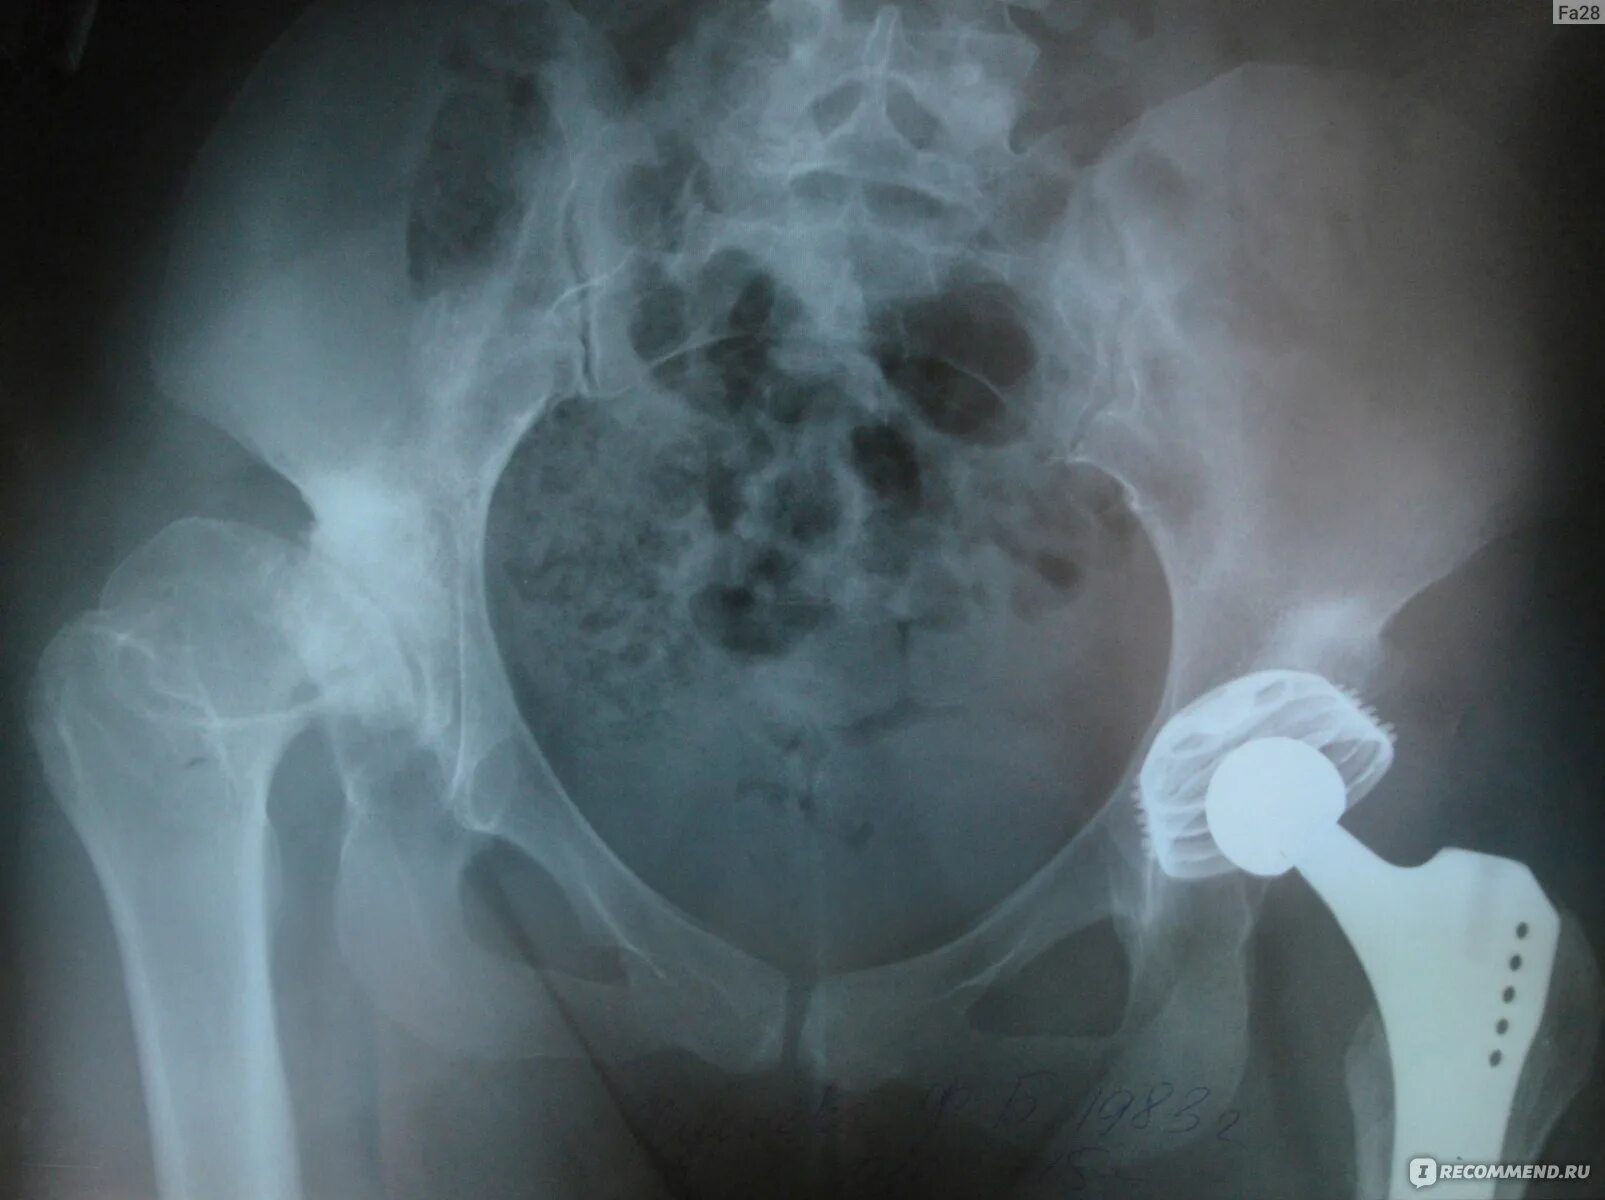

Эндопротезирование тазобедренного сустава видео